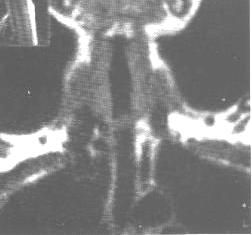

(2).CT、MRI表現:

CT、MRI能準確顯示氣管腫瘤的位置、範圍以及是否向氣管外的縱隔侵犯。良性的氣管腫瘤多位於氣管黏膜表面,氣管壁完整。腫瘤在氣管內形成軟組織密度或信號影,多為圓形,腫瘤較小,直徑2cm以下者多見。氣管壁無明顯增厚。從腫瘤的CT密度或MRI信號上來鑑別良性腫瘤的類型尚較難,但有些腫瘤具有特徵性,如脂肪瘤的密度低,CT值一般在-70HU~-90HU的範圍,MRI則在T1、T2加權圖像上腫瘤均呈高信號;富含纖維、軟骨成分的腫瘤在T2加權圖像呈低信號強度影。

氣管惡性腫瘤多發生在氣管下1/3處,以鱗癌多見,CT和MRI亦很容易顯示縱隔內腫瘤,如食管瘤、淋巴瘤、惡性畸胎瘤等對氣管的壓迫或侵犯所造成的氣管狹窄、變形和阻塞。其CT、MRI表現包括:

②管壁明顯增厚,腫瘤可沿氣管壁環形生長,或累及一側氣管壁,多見於後壁。MRI的冠狀面或矢狀面掃描能直接顯示腫瘤的上、下侵犯範圍。